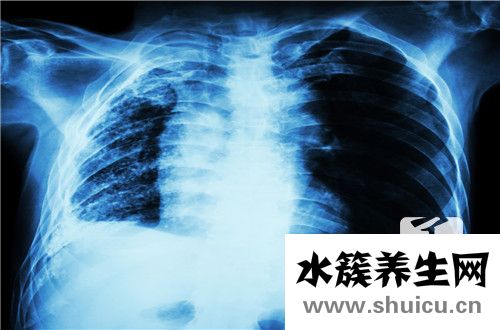

肺栓塞是由各種栓子脫落引起的。生病后會出現體力不支、面色蒼白、出汗、呼吸困難、胸痛等癥狀。部分患者肝切除術后肺栓塞發生率高。他們剛剛解決了肝臟的問題,出現了肺部的癥狀。當然,他們非常關心待遇。那么,肝切除術后肺栓塞怎么辦?下面來討論解決方案。

切肝手術后肺栓塞要依據病人的風險水平來挑選治療方法,針對低危及其中危的病人臨床醫學需要用抗凝劑來開展醫治,常見的抗凝劑臨床醫學上關鍵便是低分子肝素或是一般肝素引入。而針對上位的肺栓塞病人而言,需要立即開展栓塞治療,例如鏈激酶、鏈激酶或是是RTPA溶血栓的實際效果是十分非常好的。

肺栓塞臨床癥狀

依據栓子尺寸以及堵塞肺動脈的水平,臨床癥狀有輕和重之分:

1、具體表現

以發病忽然、大腦缺氧等一系列主要表現主導。

發病忽然,病人忽然產生模糊不清原因的體力透支、臉色蒼白、出虛汗、呼吸不暢者、胸口痛、咳嗽等癥,乃至昏厥、咯血。大腦缺氧病癥:病人極其心神不寧、害怕、惡心想吐、抽動和昏迷。亞急性疼痛:胸口痛、肩背痛、頸部痛、心前區及上腹部疼痛。總而言之,依據栓子的尺寸及堵塞的位置主要表現各有不同,但昏厥可能是急性肺栓塞惟一或先發病癥。

依據臨床癥狀可分成卒死型;亞急性心源性休克型;亞急性肺心病型;肺梗死型;突發模糊不清原因型。

2、臨床癥狀

大的動脈栓塞可出現亞急性右心衰竭的病癥,乃至猝死。心跳過速,乃至有左室期奔馬律,肺動脈第二音較為亢奮,主動脈瓣膜及肺動脈瓣有第二音瓦解,休克、紫紺、頸靜脈怒張、肝大。肺臟濕羅音、胸膜摩擦音、喘氣音及肺實變的臨床癥狀。

肺栓塞醫治